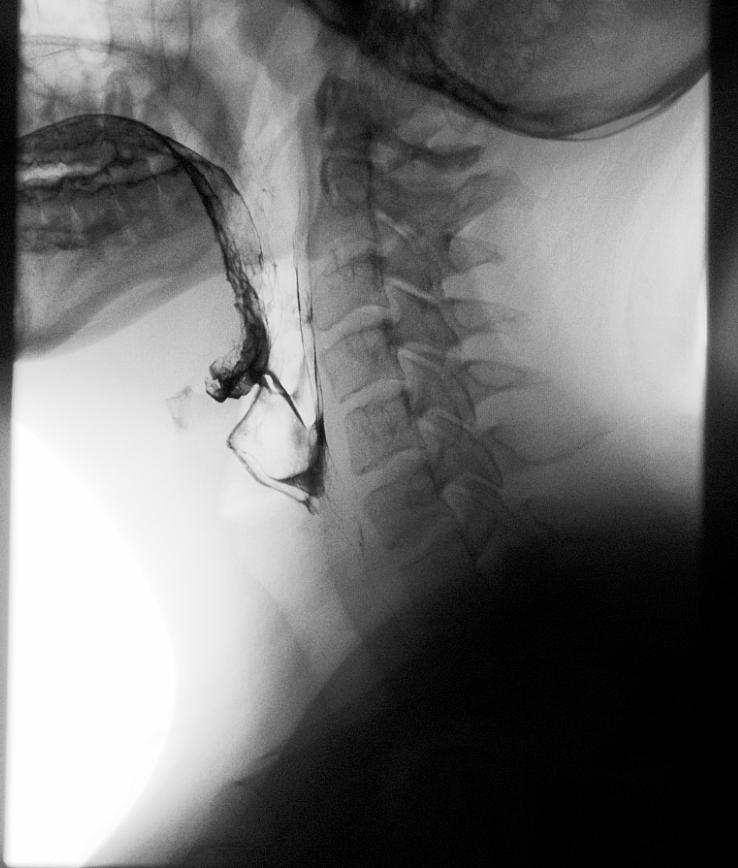

Martha Henderson is the manager of radiology services with Mercy Ships. She has a CT tech background. She holds several certifications and degrees, including MSc, BSc Diagnostic Radiography, PG Cert in CT (British). She works on MV Global Mercy (NGO Hospital Ship).

Her imaging journey started in Scotland.

“Growing up in the Highlands of Scotland, living and working in small communities has always been part of me. A friend’s mother was a radiographer, and she would show us different X-rays and the fractures identified,” Henderson recalls about her youth. “I was curious and fascinated that it was possible to learn more about the human body in this way. I graduated in 2008 and

have worked in remote and rural hospitals in Scotland. This prepared me for working with Mercy Ships as it taught me adaptability and provided a varied foundation of clinical experiences and pathology.”

“Taking the first step into international work in 2012. I always knew my path would take me into the humanitarian setting, however as a CT technologist I was not exactly sure how that would unfold,” Henderson said. “Often, surgical and medical missions rely on nurses and doctors. Finding Mercy Ships – and knowing they had a full radiology department onboard their ship – I found my calling. The organization now has two hospital ships and I feel incredibly honored to have set up the radiology equipment and services onboard.”

“Daily, I get to interact with patients from West Africa and learn about their culture and family. Volunteering on a hospital ship, you get to work alongside colleagues from around the world, to learn from their training and experiences really grows you as a professional,” she said. “Also knowing that radiology is a profession that can take you around the world and provide the opportunity for you to use your skills in many different countries and locations.”

“As the manager, I am responsible for ensuring we have highly trained CT techs who volunteer onboard, who provide CT and X-ray examinations for the patients who come onboard. This role also allows me to interact with many different radiology vendors and those collaborations are extremely rewarding,” she added.